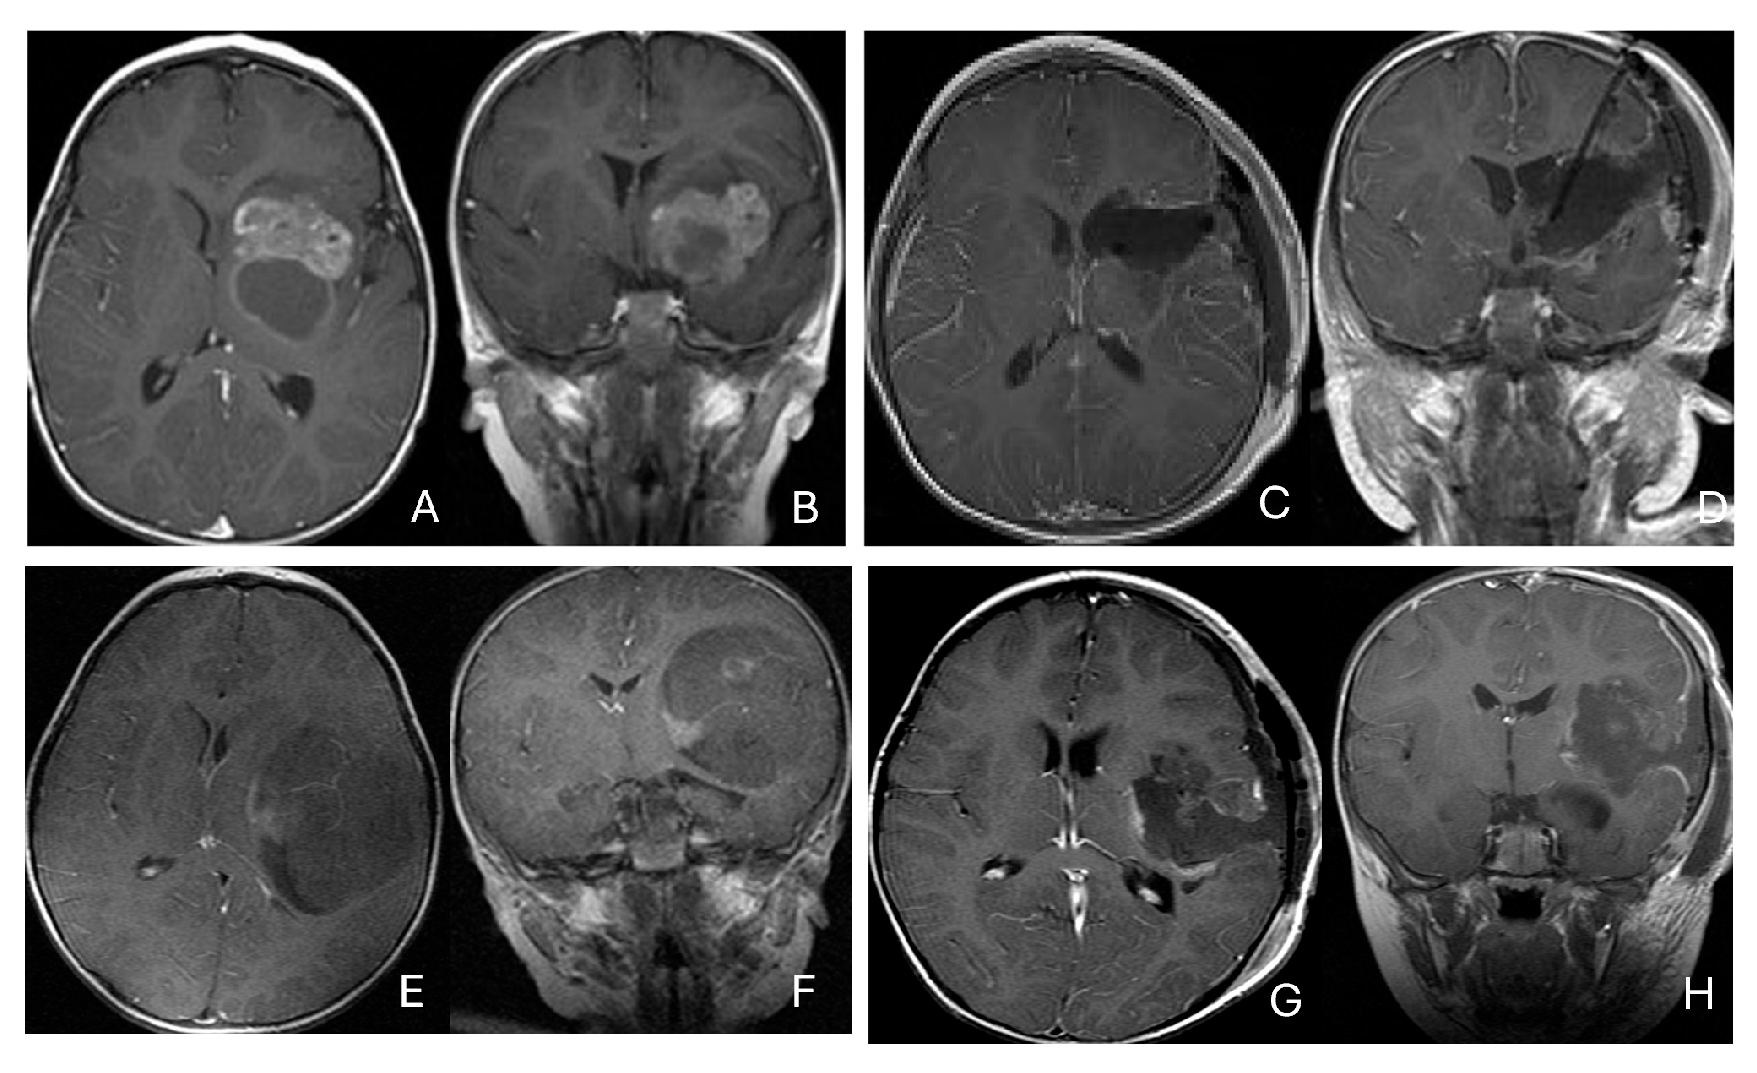

Three patients presented with massive subdural/parenchymal masses involving both cerebral hemispheres across the falx cerebri; two bi-frontal and one in bi-occipital (Figure 6). These tumors appeared to originate within the cerebral hemispheres and permeate or traverse the falx cerebri, resulting in bilateral disease.

Figure 6.

Bi-hemispheric ATRT. (A–E): MR images ((A), axial; (B), coronal; (C), sagittal) of a 4-year-old boy show a bifrontal ATRT crossing the falx cerebri, with heterogeneous enhancement. The corpus callosum is compressed posteriorly. At surgery, left frontal component invades and permeates through the falx with extension into the right subdural space. Postoperative images after bifrontal craniotomy ((D), axial; (E), coronal) show tumor resection. Bi-occipital hemispheric ATRT. (F–J): MR images ((F,G), axial; (H), coronal) of a reveal a 22-month-old girl large, inhomogeneous left occipital lobe mass crossing the midline into the right occipital lobe. The lesion invades the posterior falx cerebri and extends into the medial occipital lobe of the right side. A highly vascular tumor was resected via a left occipital craniotomy; the right occipital component was not removed with concern of blindness due to preexisting right homonymous hemianopia. She received chemoradiation with durable disease resolution for over 15 years, as shown on follow-up post-contrast MR ((I), axial; (J), coronal).

Five patients had tumors centered within the fourth ventricle; in four of these, the tumor involved the floor of the ventricle (brainstem) (Figure 7).

Figure 7.

Fourth ventricle ATRT. (A–F): MR images ((A), axial; (B), coronal; (C), sagittal) of a 21-month-old boy show a predominantly cystic fourth ventricular mass. The lesion appeared to arise from the inferior vermis, and the floor of the fourth ventricle was partially infiltrated. Postoperative images ((D), axial; (E), coronal; (F), sagittal) demonstrate gross-total resection. (G–L): MR images ((G), axial; (H), sagittal; (I), coronal) of a 3.5-year-old girl reveal a solid fourth ventricular tumor with heterogeneous enhancement. The floor of the fourth ventricle was intact, and the lesion appeared to originate from the inferior vermis. Postoperative images ((J), axial; (K), sagittal; (L), coronal) confirm gross-total resection.

In five additional patients, tumors straddled both the fourth ventricle, the lateral recess and in some further the CPA and/or the cerebellomedullary fissure (CMF), producing a dumbbell-shaped configuration (Figure 8).

Figure 8.

Fourth ventricle-lateral recess/CMFOK ATRT. (A–E): MR images ((A), axial; (B), coronal; (C), sagittal) of a 12-month-old boy show a fourth ventricular ATRT extending to the CMF through the lateral recess and with multiple peritumoral cysts. A partial invasion to the pons was noted at surgery. Postoperative images ((D), axial; (E), sagittal) demonstrate gross-total resection. Fourth ventricle-CPA ATRT. (F–J): MRI ((F): axial T2-weighted; (G): post-contrast coronal; (H): post-contrast sagittal) of a 5-month-old girl reveal a heterogeneous, dumbbell-shaped ATRT extending from the fourth ventricle into the CPA/CMF. During surgery, invasion of the lateral wall of the medulla oblongata was observed, and a subtotal resection was achieved. Post-contrast MRI ((I): axial; (J): sagittal) reveals residual enhancing tumor at the CMF.